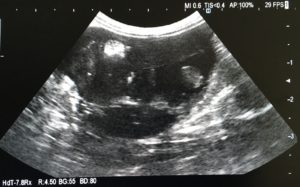

一般的な身体検査の後、膀胱と子宮の状態を超音波及びレントゲン検査で確認ました。

超音波検査所見です。子宮に大きな腫瘤(黒い部分)が確認されました。